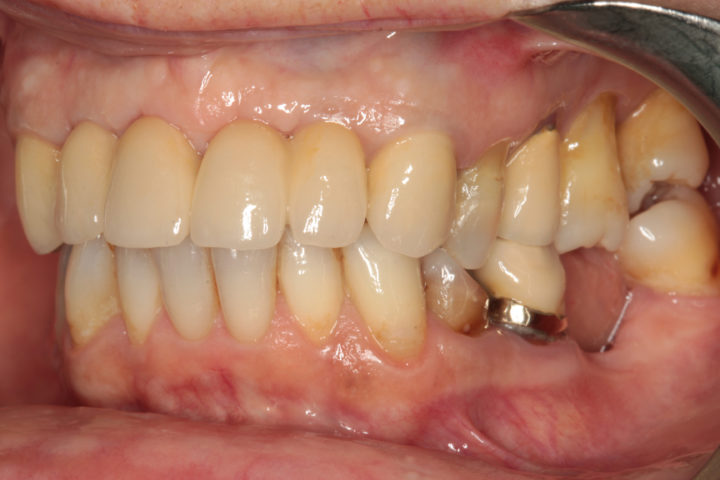

Riabilitazione di un vecchio ponte

Rimozione del ponte esistente con monconi cariati, esecuzione di estrazioni dentarie mirate, rigenerazione ossea guidata, e completamento del trattamento con un ponte in ceramica supportato da impianti in titanio.